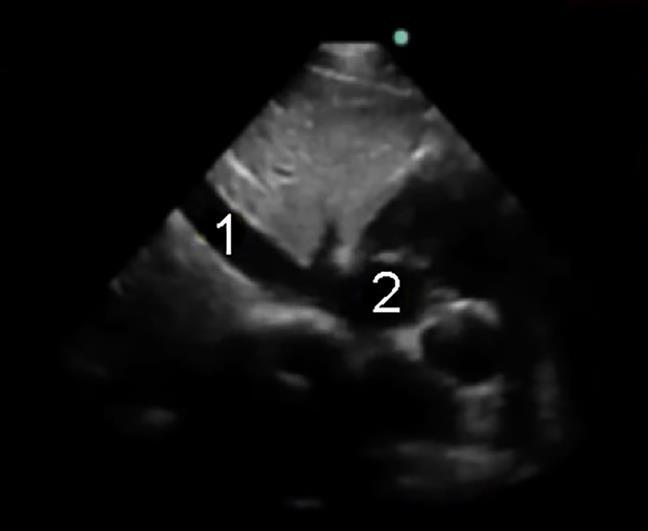

Inferior Vena Cava (IVC) Evaluation 1 Image

Inferior Vena Cava (IVC)

Right Atrium (RA)